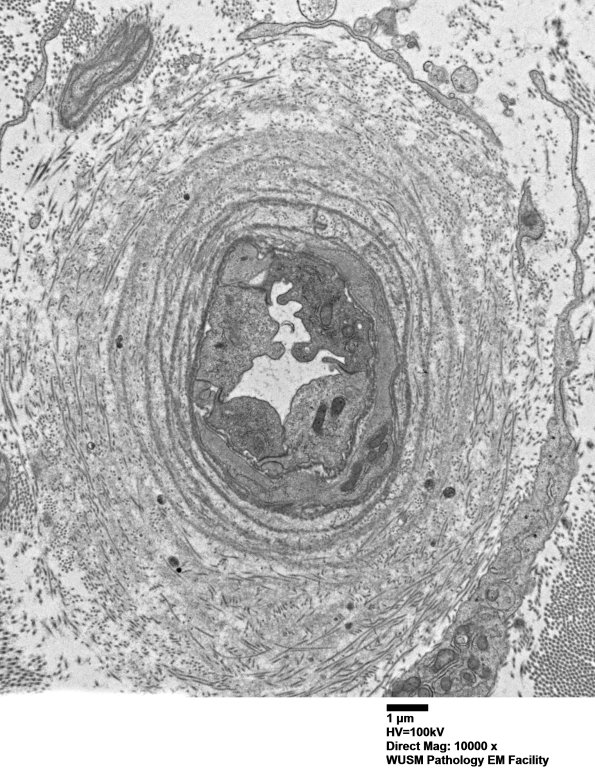

The endoneurial vessels show thickening by concentric proliferation of basal lamina. (electron micrographs)